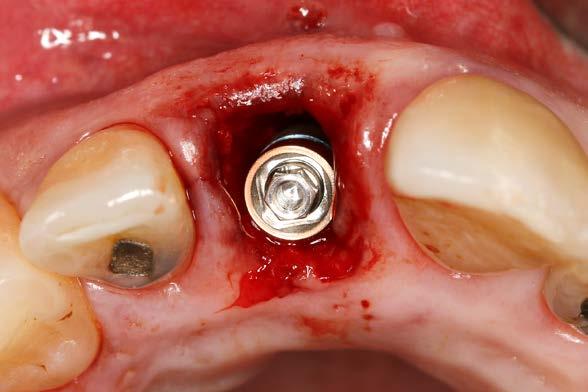

posible sobre los tejidos blandos y sobre el hueso remanente (Figura 5 y 6). Procedemos posteriormente a realizar una secuencia de fresado adaptada al lecho postextracción, alargando el alveolo con las fresas apicalmente y hacia palatino, donde se producirá el anclaje del implante. Con el lecho preparado colocamos el implante, quedándonos en vestibular el gap esperado de aproximadamente 4 mm como podemos ver en la

Figura 7. La utilización de un implante de longitud mayor y la inclinación hacia palatino nos permite lograr la estabilidad primaria necesaria para poder llevar a cabo una carga inmediata del implante. Una vez finalizada la inserción colocamos el transepitelial unitario para trabajar sobre el mismo generando la prótesis provisional de carga inmediata. Esta pieza intermedia (implante-prótesis) nos permite el uso de una interfase,

Figura 7. Imagen tras la colocación del implante ligeramente palatinizado con el gap situado en vestibular.

Figura 8. Imagen del implante colocado en el alveolo con el transepitelial unitario para llevar a cabo la carga inmediata.